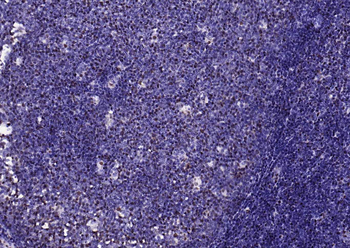

100 μl, 200 μl, 50 μlPhospho-SMAD5 (Ser463 + Ser465) Recombinant Rabbit Monoclonal Antibody [orb559123]

ICC, IF, IHC-Fr, IHC-P, WB

Mouse, Rat

Human, Mouse, Rat

Rabbit

Recombinant

Unconjugated

50 μl, 100 μlPhospho-Smad3 (Thr179) Rabbit Polyclonal Antibody [orb313112]